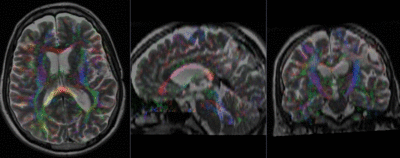

Registration Results (click to enlarge)

baseline & T2 before registration baseline to T2 after affine+nonrigid alignment DTI and T2 before & after registration